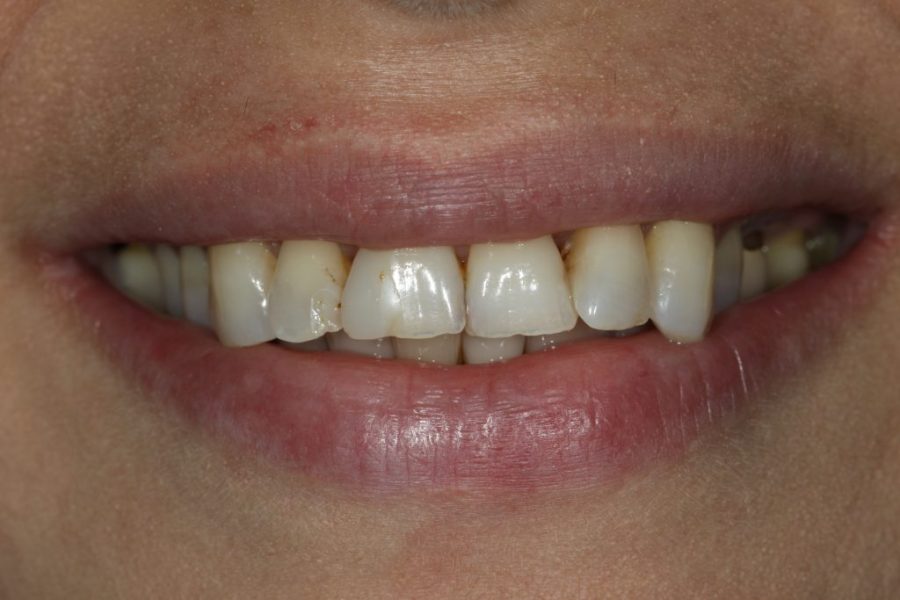

George’s Story: Customised Zirconium Bridges

George, hesitant at first, came to fix his front teeth at his wife’s insistence. After two appointments, he received zirconium bridges, giving him a full and natural smile—while preserving his signature gap.